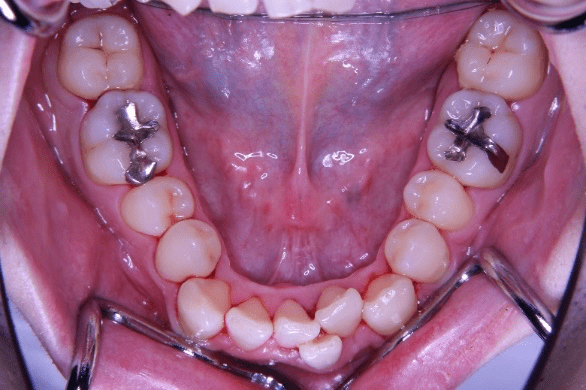

下の前歯を、顎の骨の中で無理なく排列することが出来ました

掲載症例について:

【患者】 20代男性

【主訴】 歯並びのガタガタ

【診断】 叢生

【抜歯の有無】 非抜歯

【治療期間】2年2ヶ月 通院回数18回

【治療内容】親知らずを抜歯した後、マウスピース型カスタムメイド矯正歯科装置(製品名インビザライン 完成物薬機法対象外)を使用して主訴である叢生の改善を行いました。

【費用】88万(税込)

【リスク】矯正歯科装置を付けた後しばらくは違和感、不快感、痛みなどが生じることがあります。

矯正中は矯正歯科装置が歯の表面についているため食物が溜まりやすく、また歯が磨きにくくなるため、虫歯や歯周病が生じるリスクがあります。

歯を動かすことにより歯根が吸収して短くなることや歯肉がやせて下がることがあります。

矯正歯科治療は公的健康保健の適応外の自費治療(自由診療)となります。